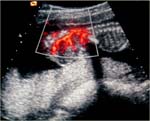

Echographiquement :    - Masse d’aspect mixte, solide ou kystique pure (15 % des cas)

- Vascularisation importante au doppler couleur